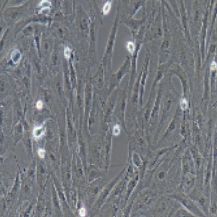

梭形细胞,不规则细胞,贴壁培养

5)细胞生长方式:梭形细胞,不规则细胞,贴壁培养。